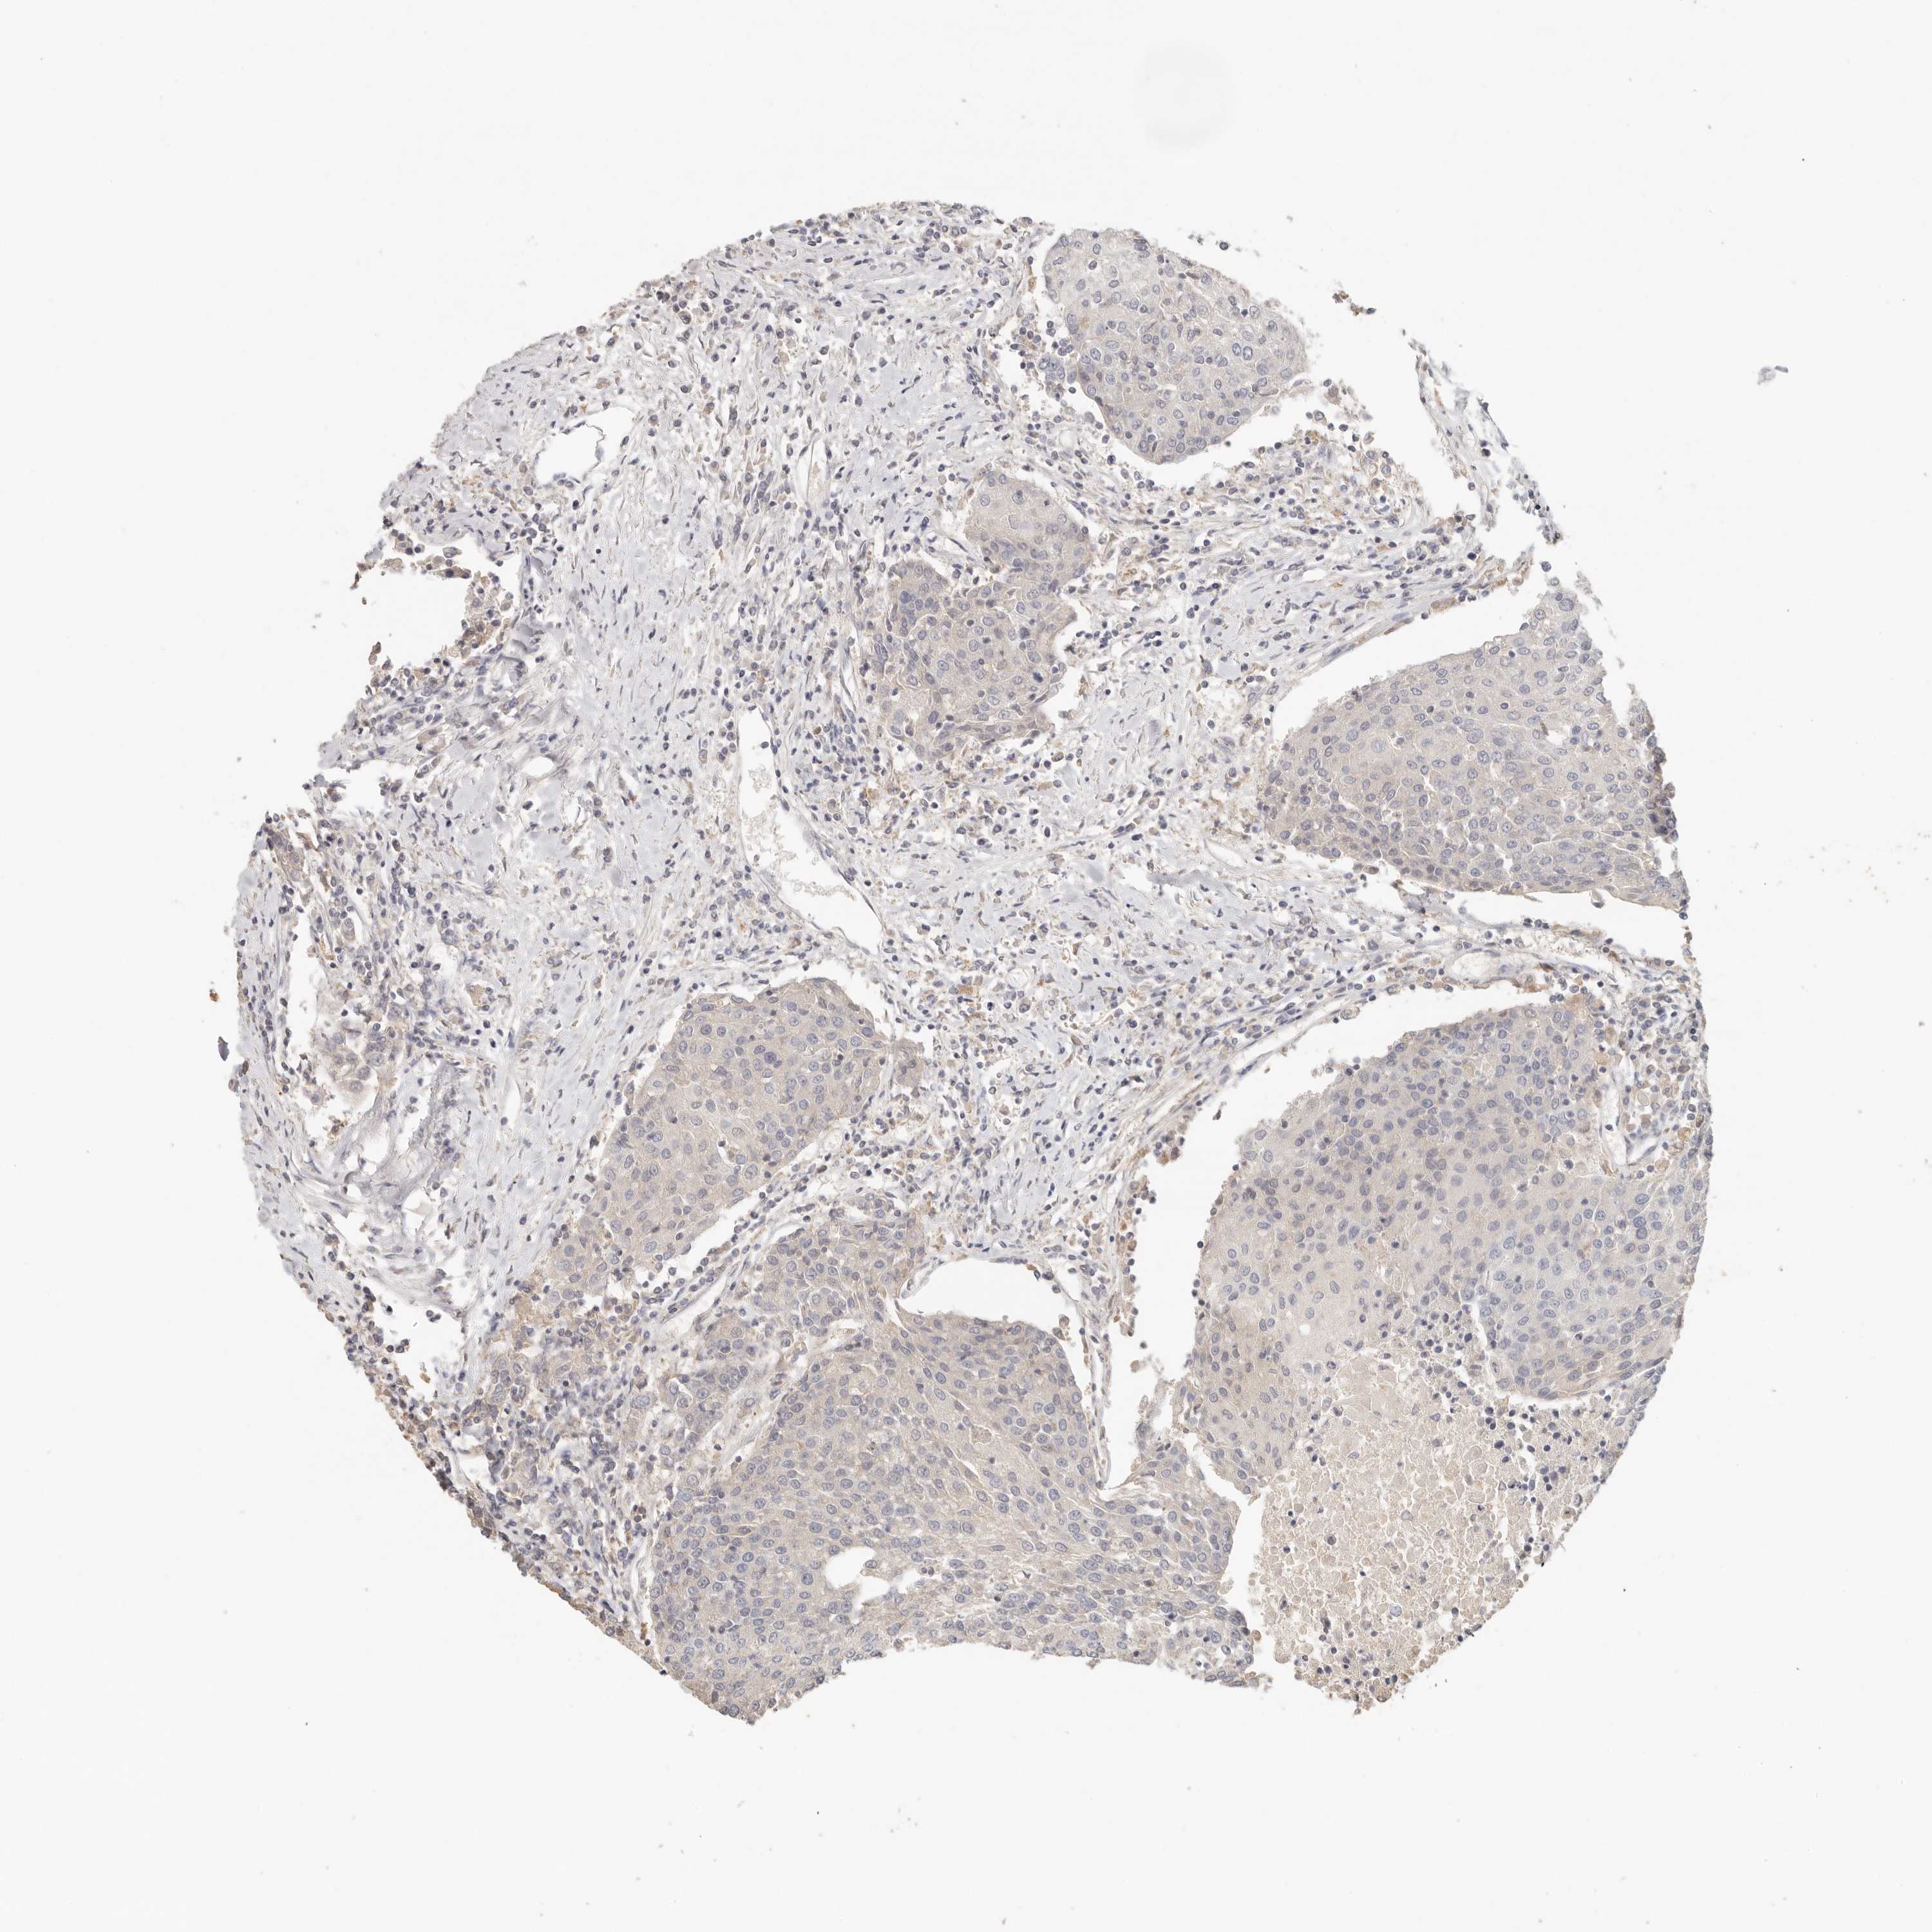

UROTHELIAL CANCER - Protein expressioni

A mouse-over function shows sample information and annotation data. Click on an image to view it in a full screen mode. Samples can be filtered based on level of antibody staining by selecting one or several of the following categories: high, medium, low and not detected. The assay and annotation is described here.

Note that samples used for immunohistochemistry by the Human Protein Atlas do not correspond to samples in the TCGA dataset.

Antibody stainingi

Antibody staining in the annotated cell types in the current human tissue is reported as not detected, low, medium, or high, based on conventional immunohistochemistry profiling in selected tissues. This score is based on the combination of the staining intensity and fraction of stained cells.

Each image is clickable and will lead to virtual microscopy that enables deeper exploration of all samples and also displays staining intensity scores, fraction scores and subcellular localization as well as patient and tissue information for each sample.

Antibody HPA026488

Antibody HPA028425

Antibody CAB011203

Staining

High

Medium

Low

Not detected

Intensity

Strong

Moderate

Weak

Negative

Quantity

>75%

75%-25%

<25%

None

Location

Nuclear

Cytoplasmic/membranous

Cytoplasmic/membranous,nuclear

Urothelial carcinoma, Low grade

Urothelial carcinoma, High grade